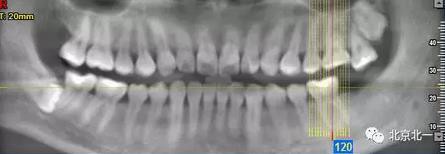

圖二:自帶的CBCT顯示下牙槽神經管貼著智齒走形。

圖三:截面圖顯示神經管位置。